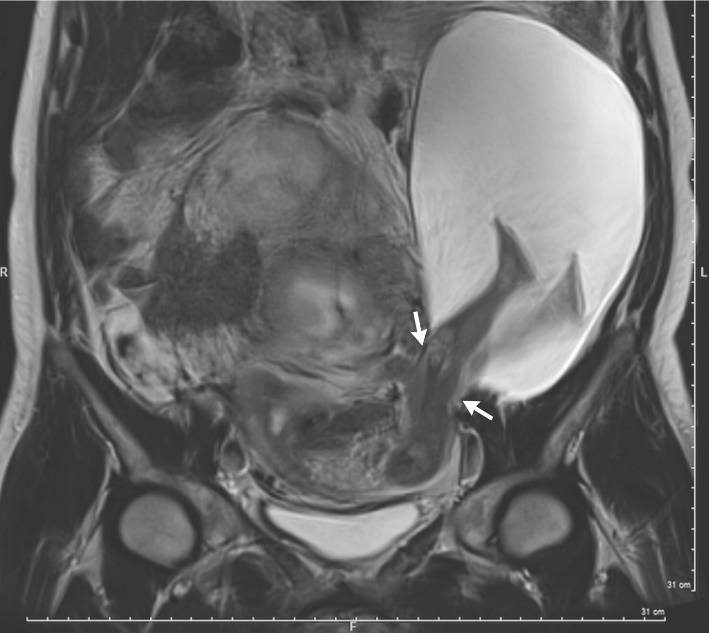

L’ecografia mostra i piedini che sporgono dopo una rottura dell’utero

Dalla risonanza magnetica sono ben visibili i piedini del figlio ancora all’interno del sacco amniotico che però è fuoriuscito per una parte dall’utero: in termini clinici, siamo davanti a un'”ernia del sacco amniotico” e a una rottura della parete uterina di sinistra di 2,5 cm.